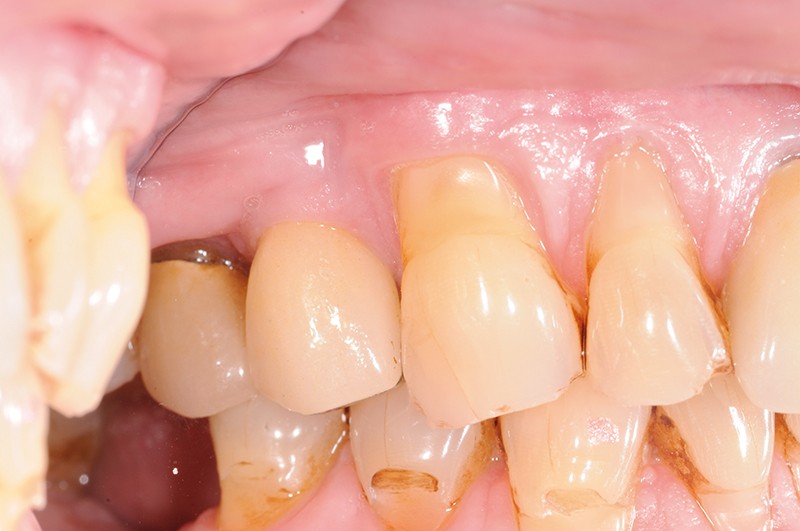

À la pose de la couronne implantaire, on notait une parfaite intégration des tissus mous(fig. 1a et b).

Lors de la maintenance de 2016, le contrôle de plaque de la patiente est toujours excellent et les tissus implantaires ne présentent pas de signes inflammatoires(fig. 2a et b).